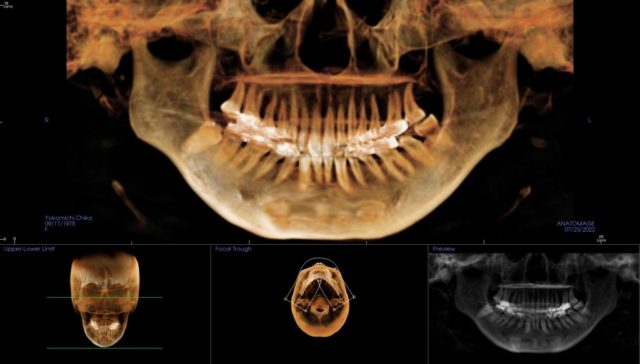

副鼻腔炎のレントゲン撮影は、CTのある医院で

1、レントゲンはCT撮影がよい

上顎洞_粘液水腫

CTのレントゲン画像です。

● 副鼻腔の中に、丸い粘液水腫があります。

● 副鼻腔の粘液水腫は、粘膜の肥厚か、粘膜の下に水が溜まっているのかは、分かりません。

● 白くなり、水か粘膜である事がわかります。

真っ白というほどではありません。

● 副鼻腔炎なしの場合は、レントゲン画像は黒くなり、空気が入っているのがわかります。

3、パントモレントゲン

上顎洞炎撮影のレントゲン_パントモ

CTから再構成した

パントモレントゲン像です。

副鼻腔炎がわかるほどでは、ありません。

パントモ専用機は、鮮明に写りますが、

CTから再構成したパントモ像は、

そこまで鮮明ではありません。

一番よく分かるのはCT

副鼻腔炎は、

CT撮影が一番よく分かります。

どの歯の、

どの歯根が原因か、

その歯根の長さは何ミリか、

などが分かります。

歯性上顎洞炎の時は、最低でも、CTのある歯医者さんで、治療してください。